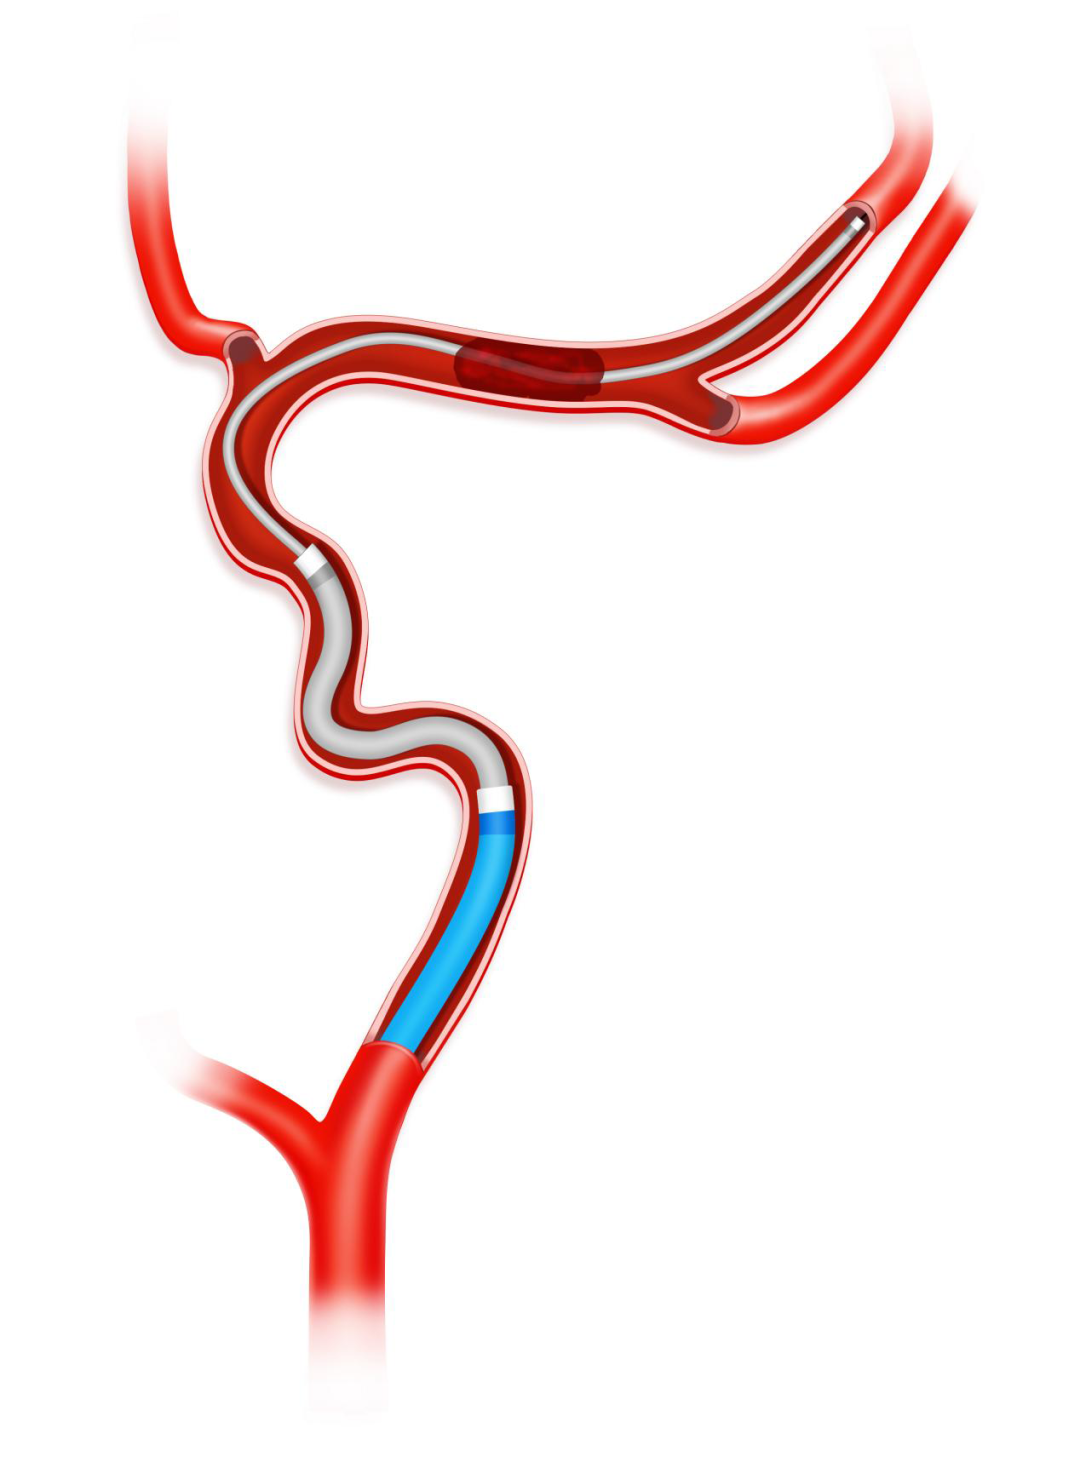

沿17或21系列微导管输送并释放3.0*25mm Syphonet®取栓支架,支架近段覆盖大脑中动脉闭塞病变部位,支架远端到达大脑中动脉M2。利用Syphonet®取栓支架的锚定作用和远端防血栓逃逸保护作用。

Syphonet®取栓支架锚定作用下跟进Tethys AS®血栓抽吸导管,靠近血管病变处开始关掉滴注,打开血栓抽吸导管Y阀后,越过大脑中动脉闭塞处到达大脑中动脉M1段末端。